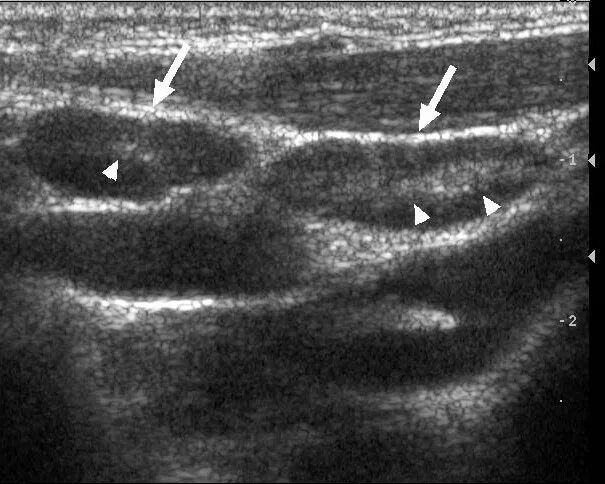

Метастазы в паховых лимфоузлах